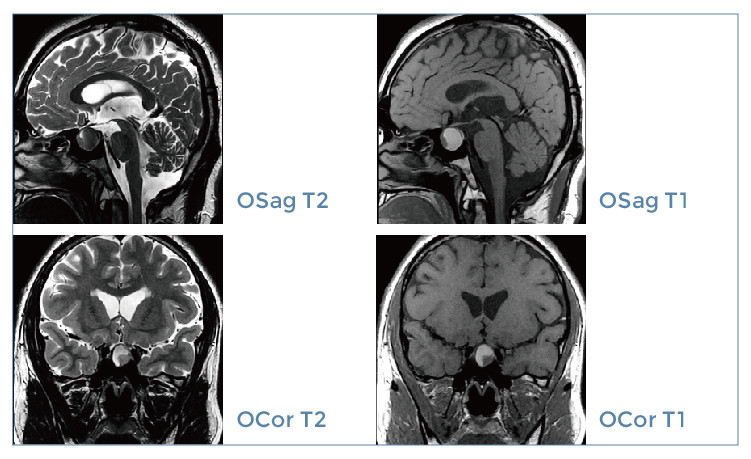

【朗润影像档案】磁共振影像病例分享(编号20200104)